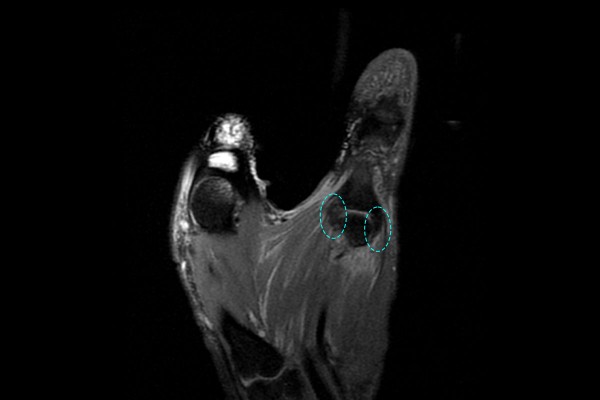

자세한 검사를 위해 MRI 검사를 진행하였고, 판독 결과 엄지손가락 우측부분에는 까만 인대가 확인되지만, 좌측 부분에는 까만 인대가 보이지 않았고, 좌측 손 엄지 중수-수지관절 척측측부인대 파열(Lt. hand 1st Ulnar collateral ligament rupture [stener lesion])로 진단되었습니다.

*stener lesion - 힘줄이 걸려서 치료되지 않는 것